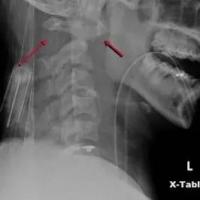

• 颈椎骨折

• 颈椎骨折护理常规

颈部颈椎骨折

• 颈椎骨折截瘫病人康复指导

• 颈椎十类骨外伤X片,看一遍秒掌握